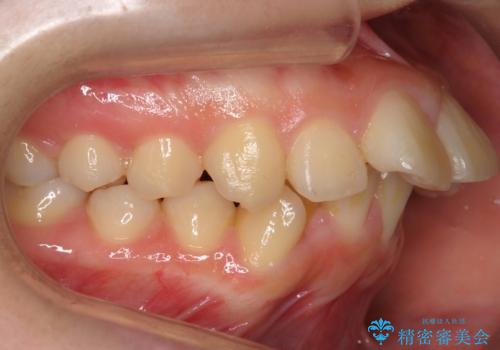

20代女性 出っ歯 口元を引っ込めたい

- 出っ歯と前歯を気にして来院。

口元を下げたいとのことで、歯を抜いてワイヤー矯正を行いました。

上下左右の小臼歯を抜歯しています。